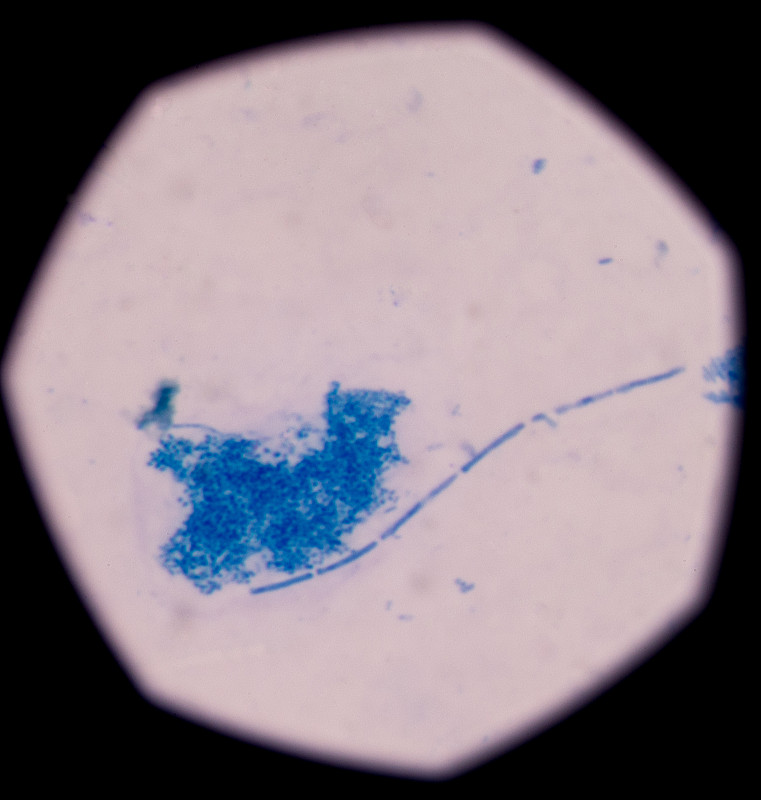

结核分枝杆菌详情

结核分枝杆菌详情

结核分枝杆菌详情

结核分枝杆菌详情

结核分枝杆菌详情

结核分枝杆菌的详情